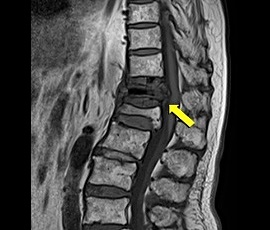

[非血管系IVR] 圧迫骨折(胸椎) 手術:経皮的椎体形成術(PVP)

MRI画像

治療後